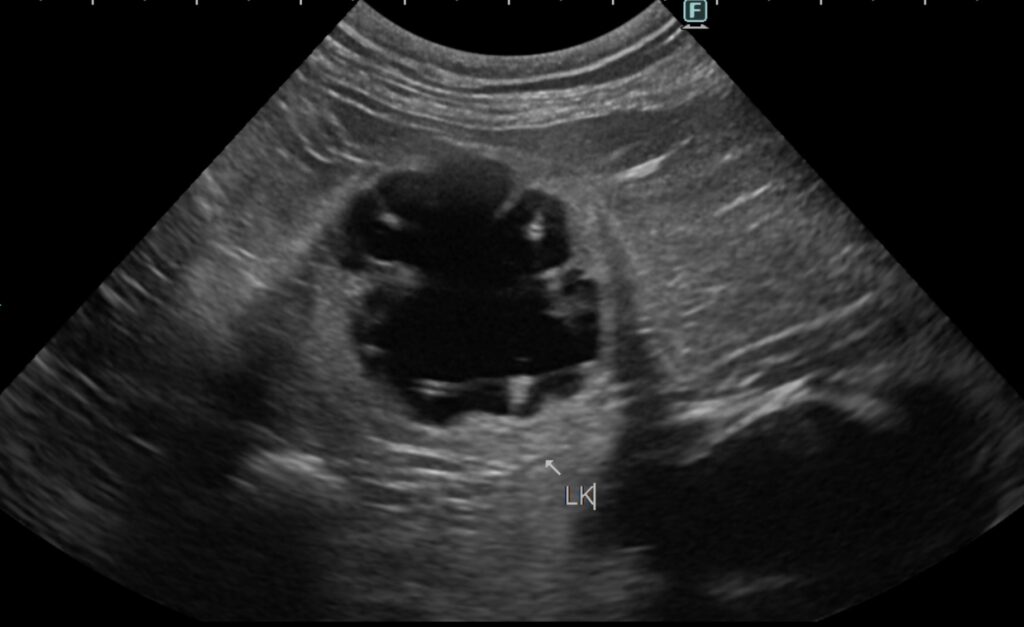

エコー検査より、両側の重度腎盂拡張、右腎臓の尿管拡張の所見が認められる。

右腎臓は6cm大に腫大、左腎臓は2cmに萎縮。